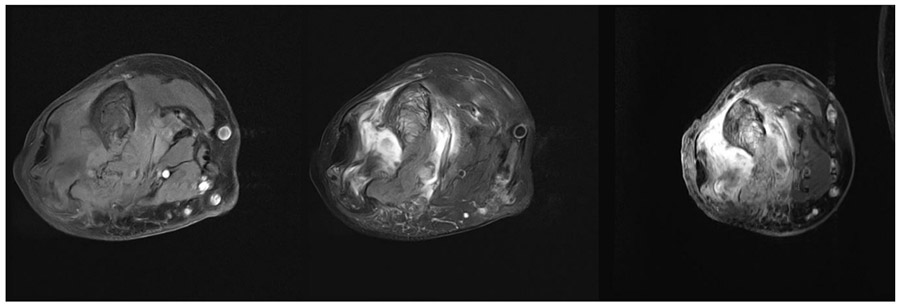

Before the surgery: The MRI shows significant damage in the same area and widespread surrounding edema.